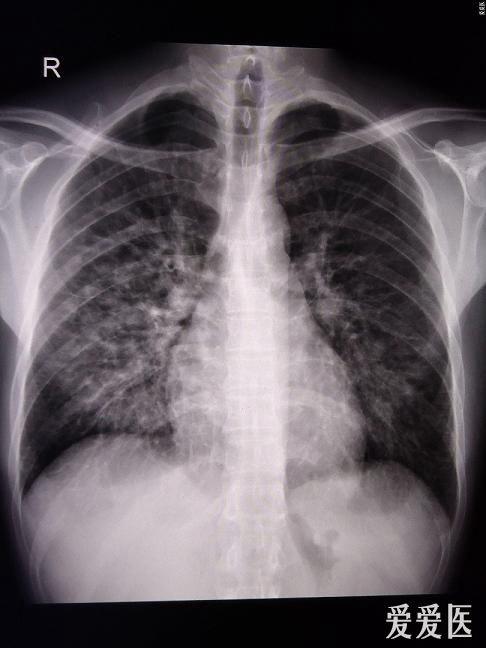

肺部ct帮助诊断